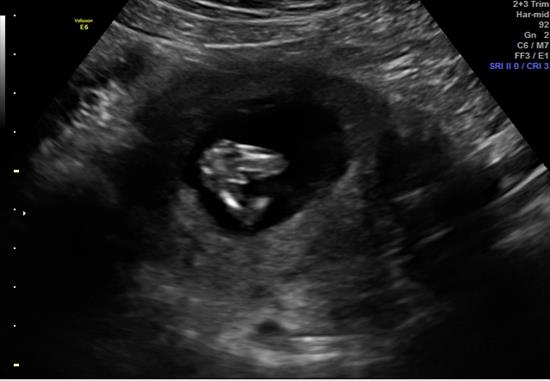

BABY is 12 weeks 4 days...

Pink or Blue?

Also -- saw this between the legs, boy parts???